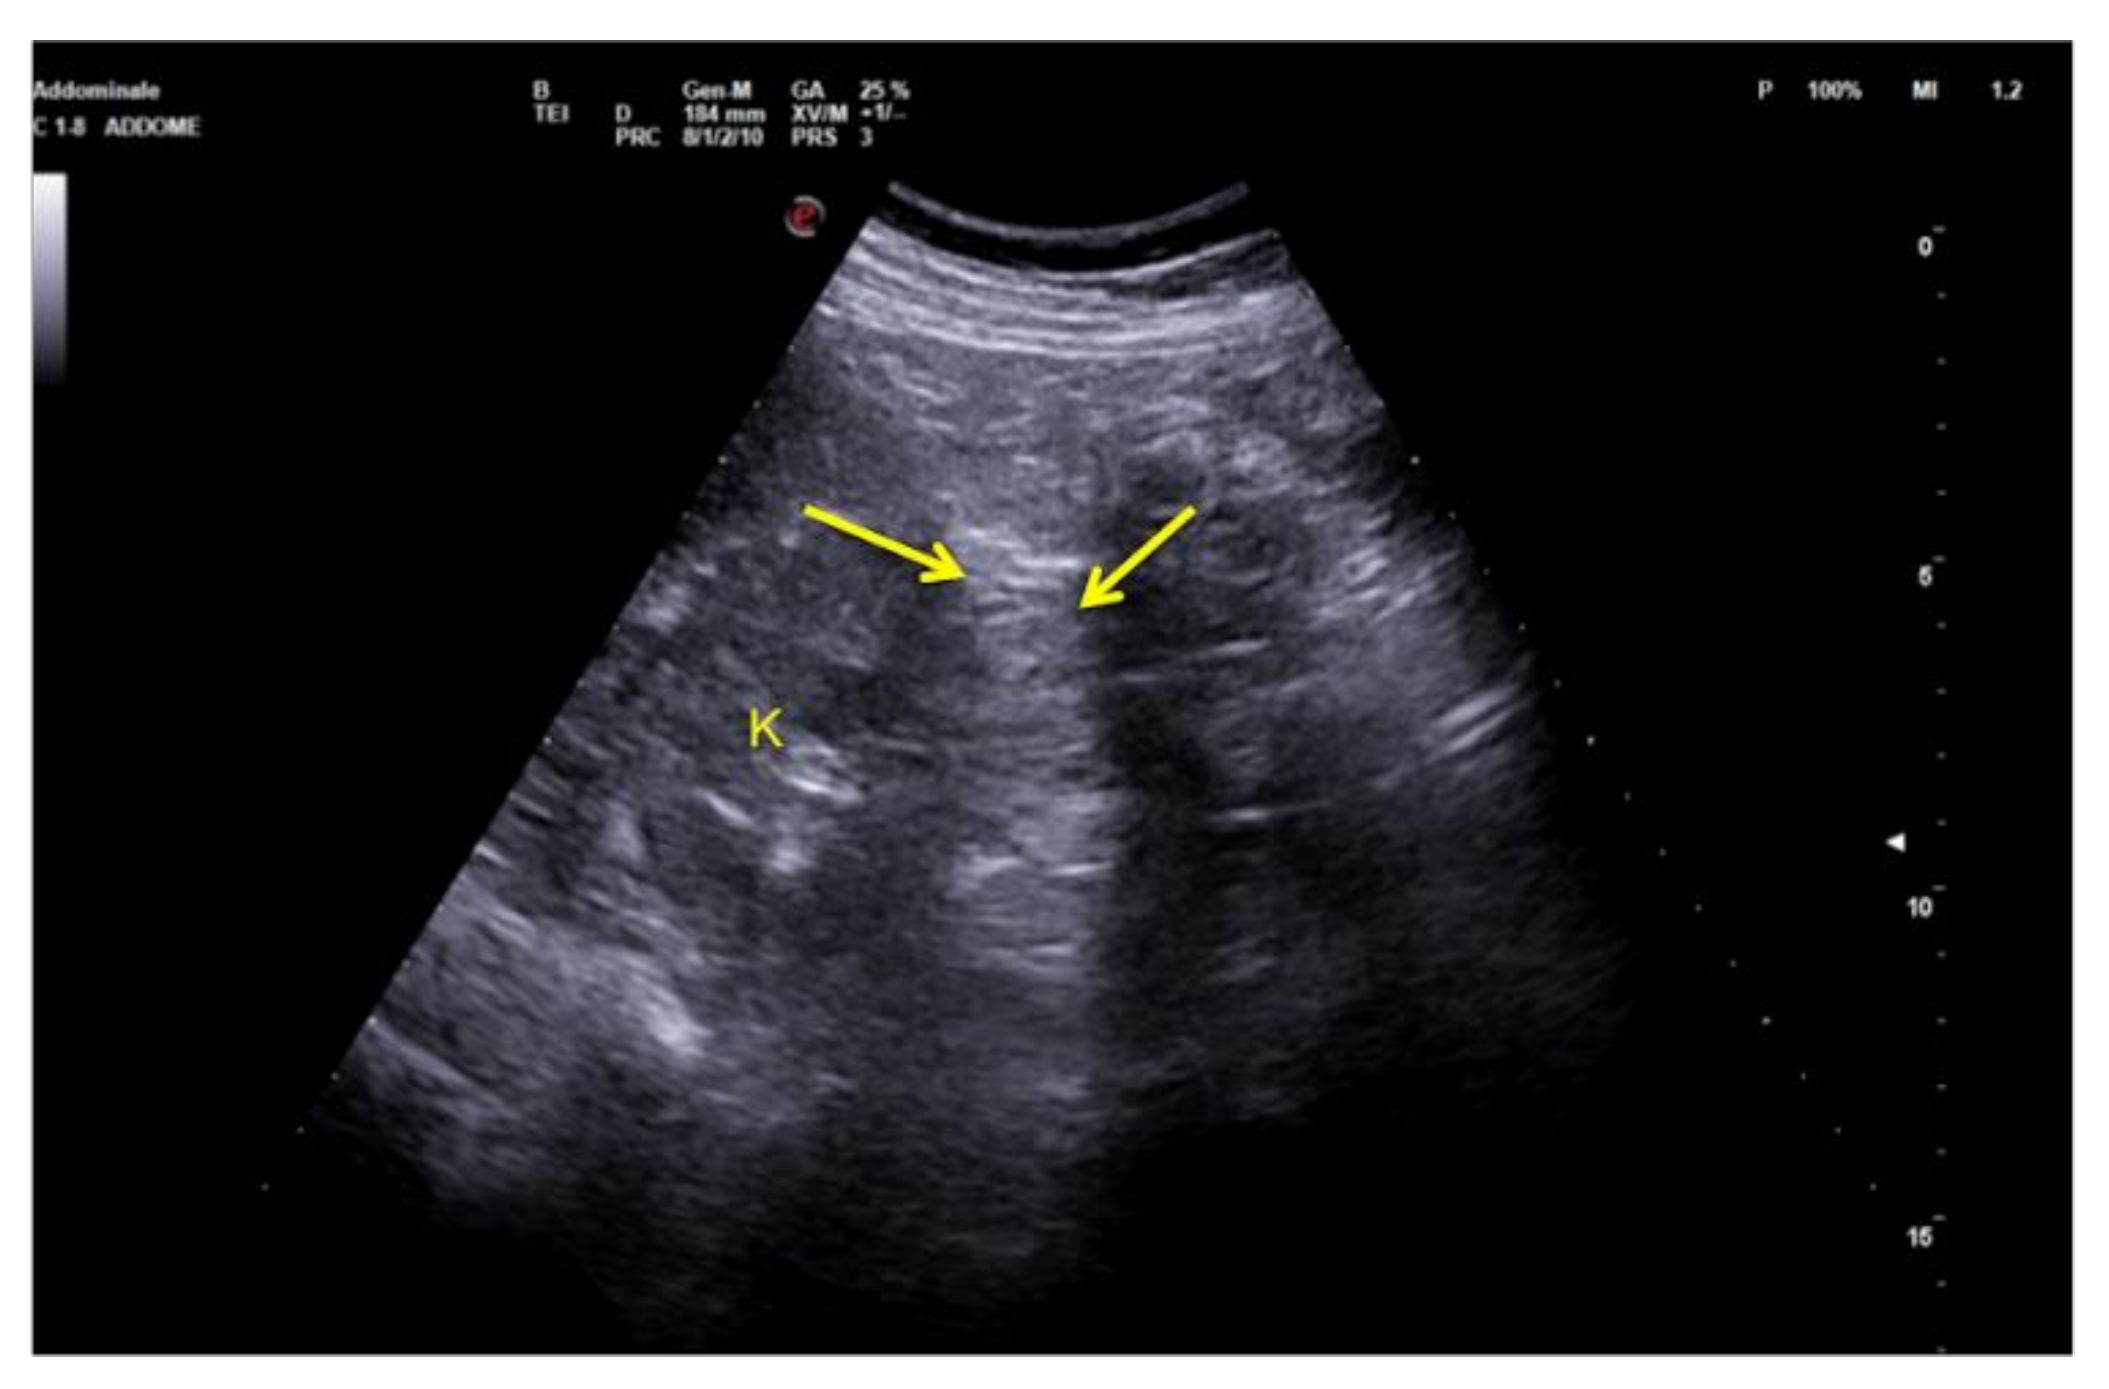

3.1.4. Refraction Artifacts